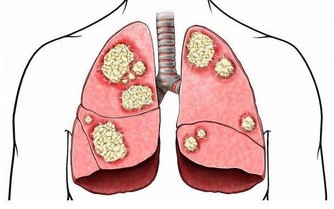

- 自體免疫性疾病:如多發性硬化症或類風濕性關節炎,這些疾病可能攻擊神經系統,導致麻木感。